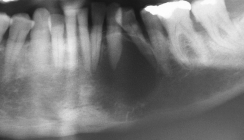

Die intraorale Manifestation zeigt parallel zu den Verhornungsstörungen schwere entzündliche Veränderungen am Zahnstützgewebe, schon kurz nach dem Durchbruch der Milchzähne. Es kommt zu akuten Entzündungen der Interdentalpapillen und der marginalen Gingiva, die zur Bildung von Zahnfleischtaschen führen, aus denen sich Pus entleert. In kurzer Zeit entwickelt sich eine Parodontitis marginalis profunda, die je nach Ausprägungsgrad des Syndroms zu einem Ausfallen der Milchzähne bis zum vierten oder fünften Lebensjahr führt.58 Im zahnfreien Intervall zwischen dem Verlust der Milchzähne und dem Durchbruch der bleibenden Zähne ist die Alveolarmukosa weitgehend unauffällig. Nach Durchbruch der bleibenden Zähne wiederholt sich der oben beschriebene parodontale Destruktionsprozess, sodass auch die bleibenden Zähne bis zum 15. Lebensjahr verloren gehen. Die Weisheitszähne bleiben verschont.52,58 Röntgenaufnahmen zeigen analog zum klinischen Befund massive Osteolysen der alveolären Knochenstrukturen.59